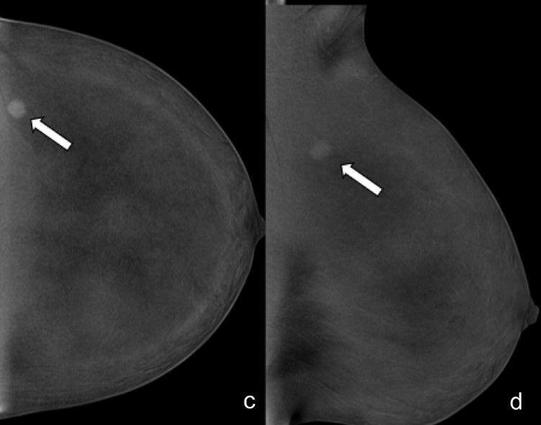

Misdiagnosis in breast imaging can delay treatment, cause unnecessary procedures, and erode patient trust, leading to worse prognosis and raise healthcare costs.

How do we address this? Accurate imaging, continuous education, and clear communication among providers are key to minimizing risks and improving patient care. (Isabelle Thomassin-Naggara et al.)